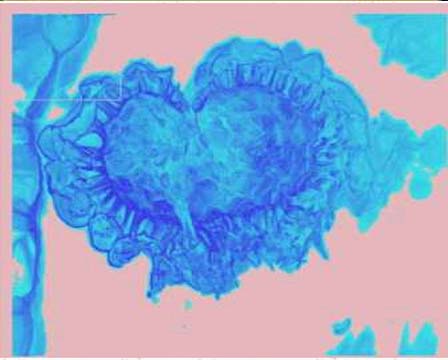

LCSM IMAGES

LCSM IMAGES[Laser Scanning Confocal Microscope System]